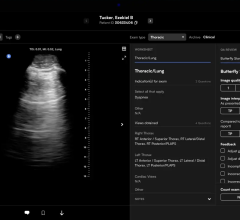

January 31, 2023 — Esaote, a leading Italian company in the biomedical sector – in ultrasound, dedicated MRI and medical ...

Radiology departments have many different needs and face a wide variety of challenges that can impact their departments ...